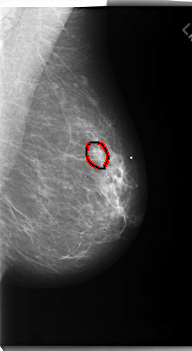

FILE: C_0170_1.LEFT_MLO.OVERLAY

TOTAL_ABNORMALITIES 1

ABNORMALITY 1

LESION_TYPE MASS SHAPE OVAL MARGINS SPICULATED

ASSESSMENT 5

SUBTLETY 4

PATHOLOGY MALIGNANT

TOTAL_OUTLINES 1

BOUNDARY